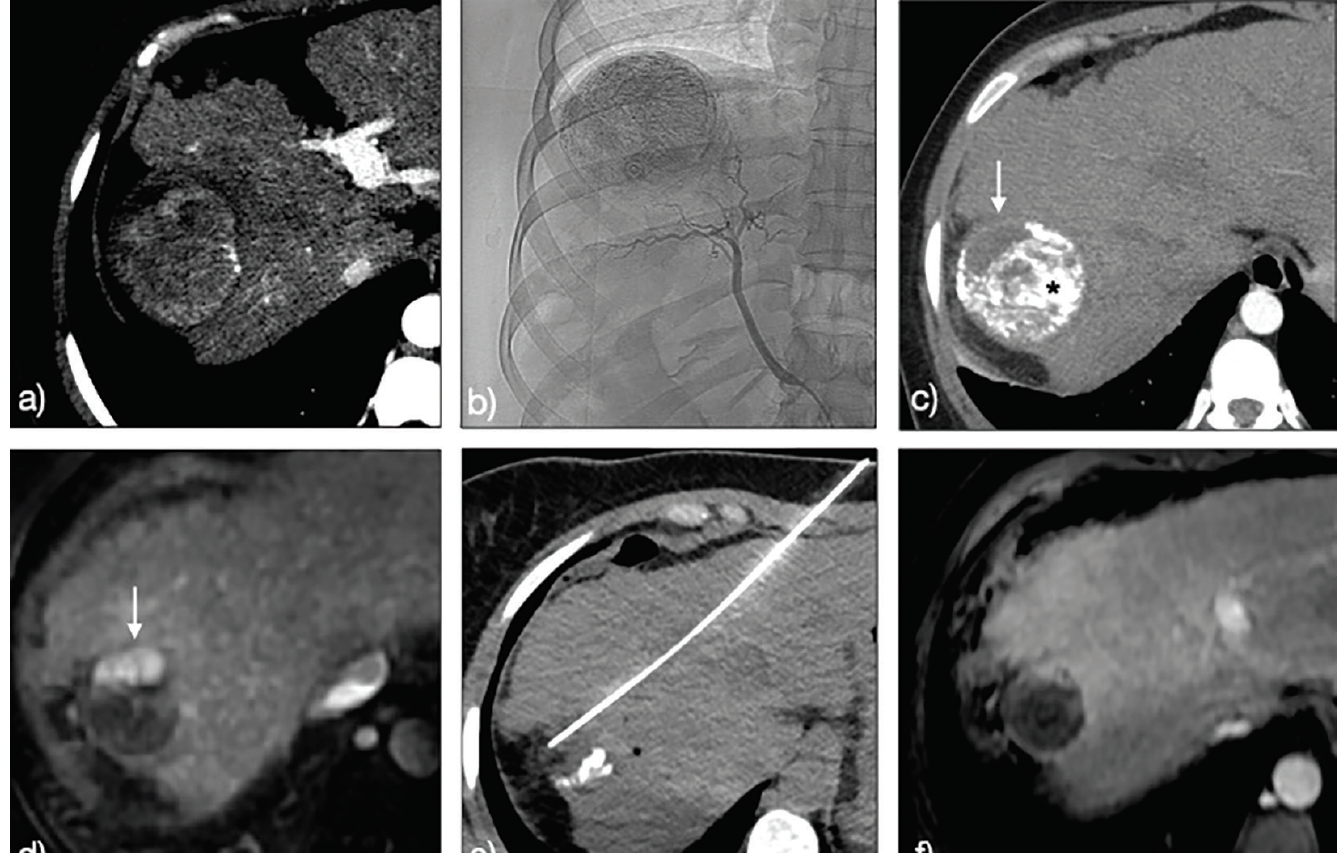

A thought-provoking installment of Clinical Quandaries is presented by Alejandro Gabutti, MD; and Tommaso Cascella, MD, of a 36-year-old patient with hepatitis C virus-related cirrhosis and a subsequent diagnosis of hepatocellular carcinoma.